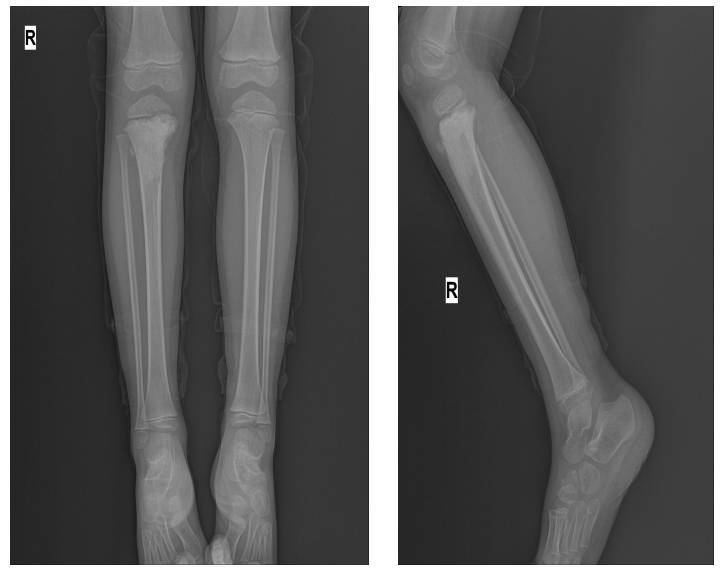

Ameliyat Öncesi: Röntgende proksimal tibiada düzensiz sınırlı sklerotik lezyon görülmekte